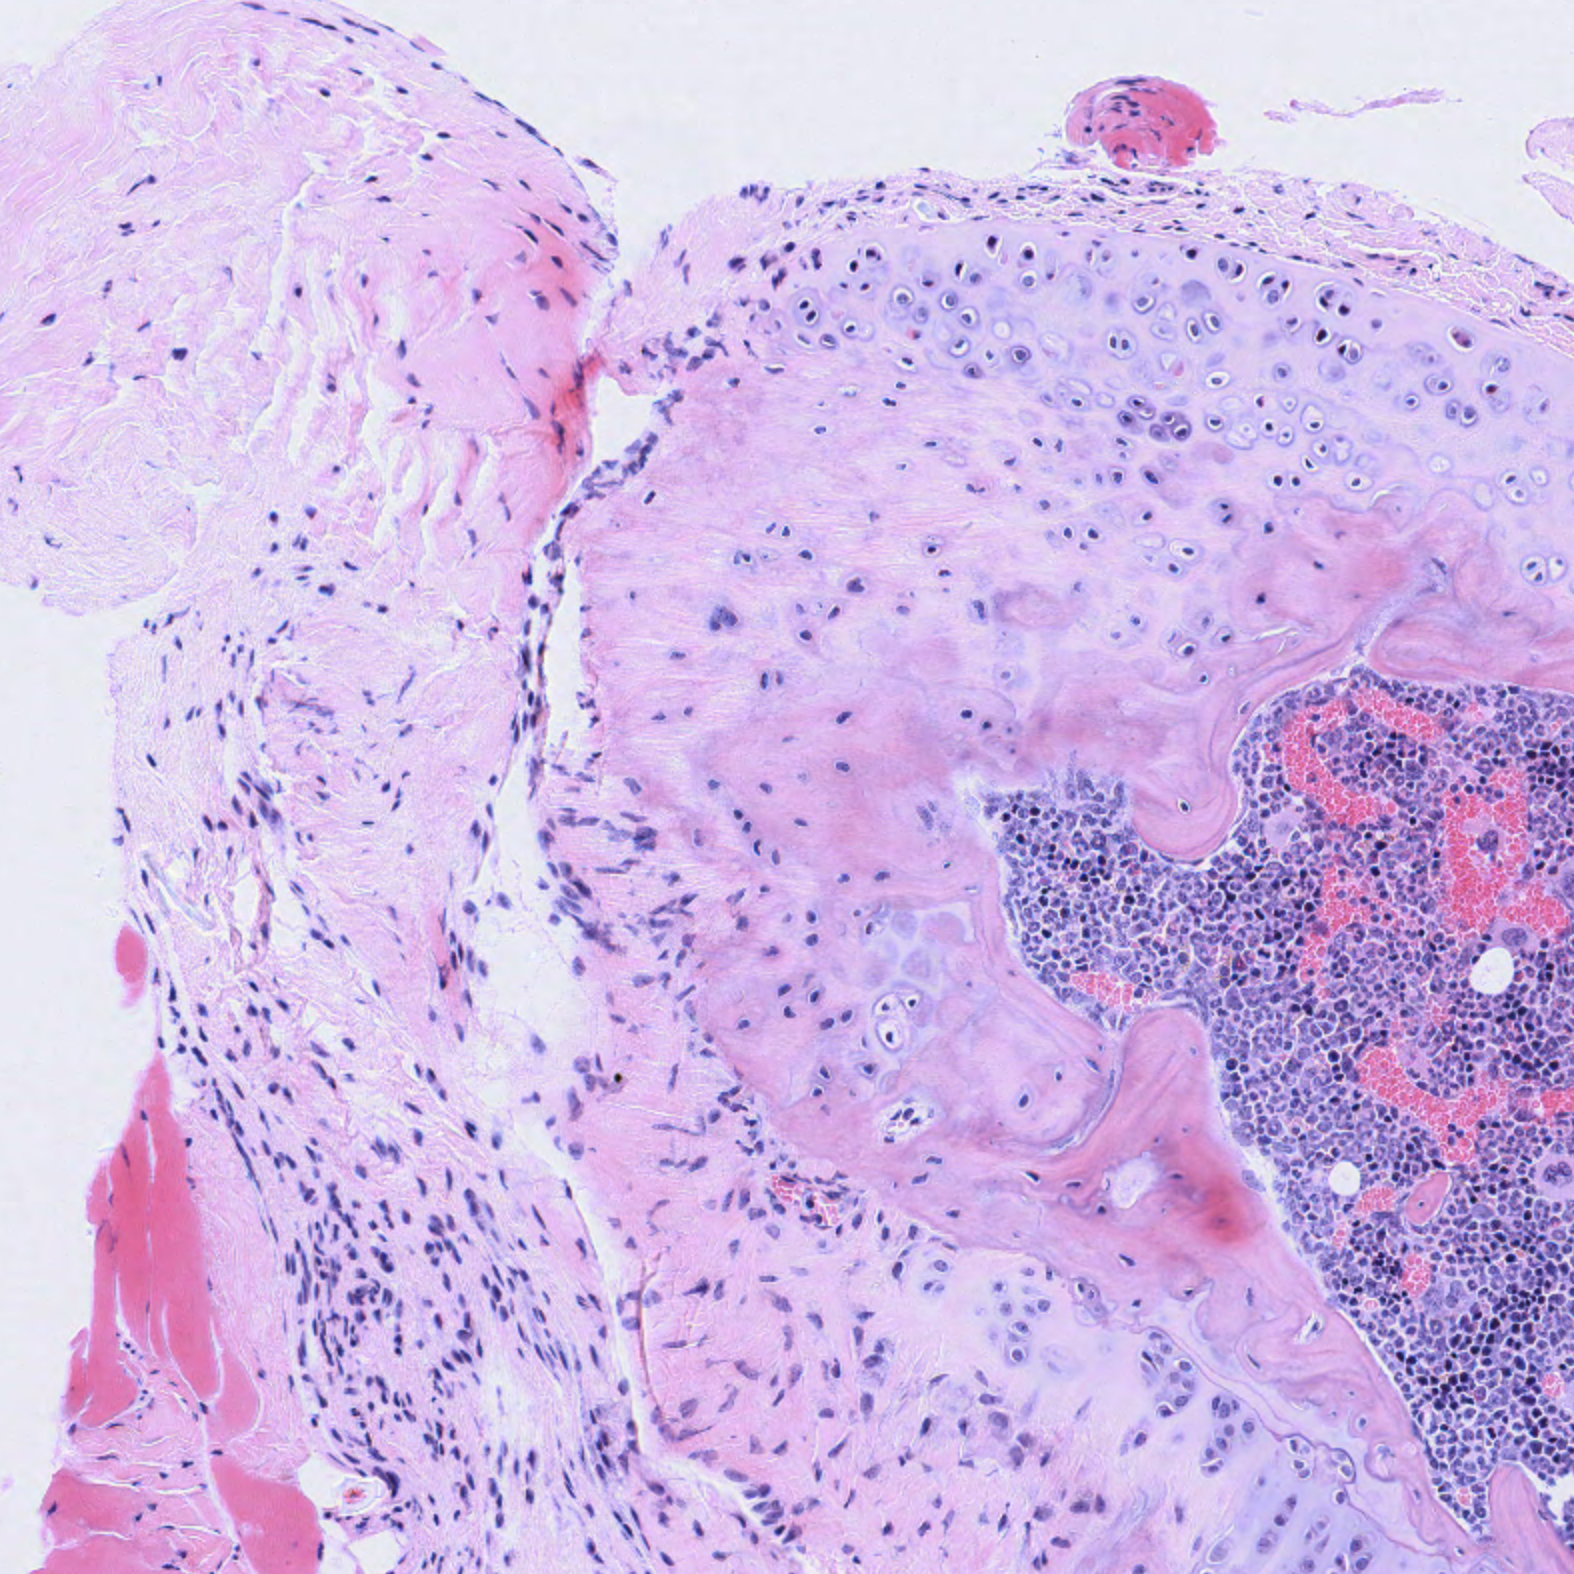

| Tibia_Epiphysis_H&E_02.svs Tibia_Epiphysis_H&E_02.png |

The blue colour in the pentachrome stain kit represents mucin and indicates the progression of bone remodelling. The pentachrome stain kit helps to visualize the bone material before ossification. Chondroids and the matrix are also well differentiated and visualized. Further, striations of the muscles, bone, and cartilage are well visualized with the pentachrome stain kit.